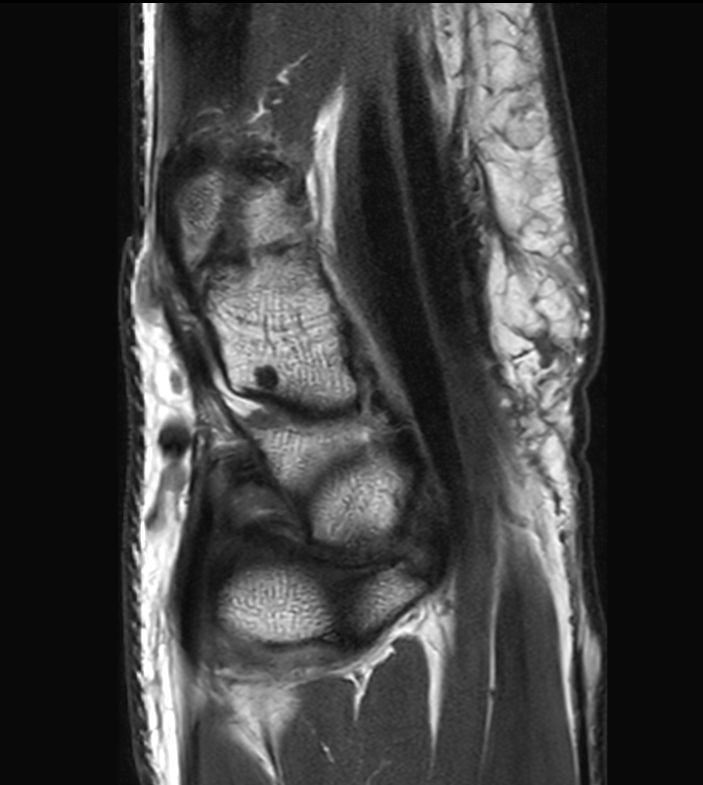

Off-center imaging of the Wrist with the dS HandWrist 16ch coil. Compressed SENSE is used to speed up the entire exam with virtually equal image quality.2.